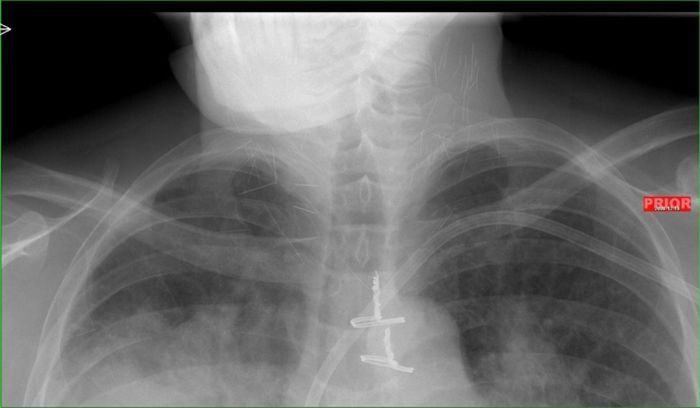

Рентген показал, что у чувака в шее огромное количество иголок.

Оказалось, что товарищ - нарк со стажем и все эти иглы остались в шее после неаккуратных инъекций.

Парня подлечили, конечно. Но иглы он отказался вытаскивать, так как он их типа любит и привык к ним.